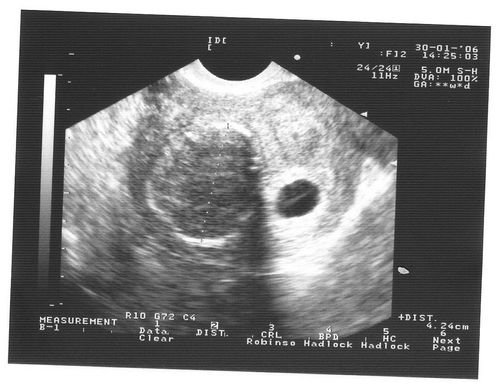

На 6 тижні вагітності по фото УЗД розмір плода встановить абсолютно чітко - це зовсім малесеньке, але вже цілком жива істота. Розмір плода фото УЗД показує дуже добре. Він досягає, всього на всього, 1,5 см. Саме на шостому тижні починають формуватися нервові закінчення в ручках і ніжках, а нервові клітини займають свої місця по всьому організму. Це говорить про те, що малюк скоро почне все відчувати, і буде поступово вчитися рухатися. За допомогою УЗД на цьому тижні вагітності лікар перевірить важливу особливість - як розвивається головний мозок плоду. До цього часу всі три частини «розумового відділу» дитини повинні бути сформовані. Фото УЗД допоможе виключити патології. Розмір плода фото УЗД для досвідченого лікаря може багато про що рассказать.Особенно це важливо, якщо є сумніви в правильному розвитку. З'являються невеликі пухирці, які незабаром стануть чудовими очима. Дивно, але зір - це той важливий орган, який буде формуватися протягом всієї вагітності і завершиться тільки після пологів. Починають формуватися легкі. В організмі все відбувається поступово, для кожного процесу є свій термін. Але завдяки таким знанням, ви можете, нарешті - то усвідомити, що всередині вас перебуває справжнє живе диво - ваш майбутній малюк. І нехай зараз - на шостому тижні, він зовсім не схожий на немовля, він вже є таким.

Розмір плода фото УЗД на даному терміні вагітності показує чітко і ясно. Але крім того УЗД в першому триместрі вкрай важливо для встановлення наявності патологій і загроз для життя як матері так і ребенка.Но все ж варто пам'ятати і про те, що не варто робити фото УЗД без показань лікар, а просто з цікавості побачити майбутню дитину. Справа в тому, що навіть якщо ви хочете побачити свою майбутню дитину цьому тижні вагітності, то вам це навряд чи вдасться.

Фото УЗД покаже, що на цьому тижні протікання вагітності розмір дитини досягає невеликої горошини. Але завдяки тому, що медицина сьогодні пішла далеко, УЗД може встановити розмір плода з точністю до міліметра. Як відбуваються виміри?

Для початку у малюка необхідно знайти куприк і визначити тім'яну зону. На фото УЗД це буде абсолютно невелику відстань, але все ж і його можна виміряти. Відстань між цими зонами називається довгою плода і на шостому тижні вагітності досягає всього пари міліметрів.

Фото УЗД розмір плода визначає точно і це важливо для першого триместру. Саме перше проведене УЗД допоможе лікарю встановити найбільш точний термін пологів. Це важливо в тому випадку, коли у вагітної до пологів не була регулярний або непостійний менструальний цикл або вона просто не пам'ятає необхідних дат. В основному, на шостому тижні УЗД проводиться для того, що б встановити достовірність вагітності - її наявність. До цього терміну матка починає збільшуватися і фото УЗД фіксує ці зміни. Для того, що б більш точно встановити розмір плода і термін вагітності за допомогою УЗД також проводять дослідження плодового мішка. Допоможе у встановленні термінів і серцебиття вашого малюка. Апарат УЗД вловлює скорочення сердечка, виводить їх на екран і динамік. Мама може насолоджуватися, а лікар завдяки цим звукам встановить термін розвитку ембріона, яким повинен бути розмір плода і визначить за допомогою УЗД безпосередньо сам термін вагітності і дату можливих пологів.